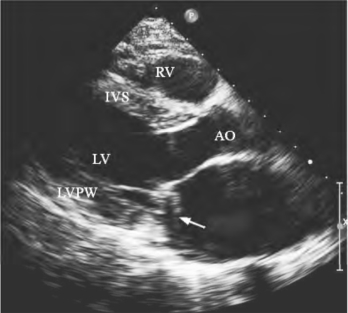

图13-11 二尖瓣腱索断裂二维超声图

收缩期断裂腱索进入左房(箭头所示)

(1)二尖瓣叶与腱索连续中断:瓣叶的游离缘与断裂的腱索残端相连(图13-11),断裂的腱索随瓣尖活动呈不规律的异常运动。(2)断裂腱索回声:收缩期左房内显示断裂腱索回声,并在左房内漂浮活动。若为细菌性心内膜炎引起者,可显示瓣尖增厚、断裂腱索增粗、回声增强或附着条状、团状异常回声(图13-12)。